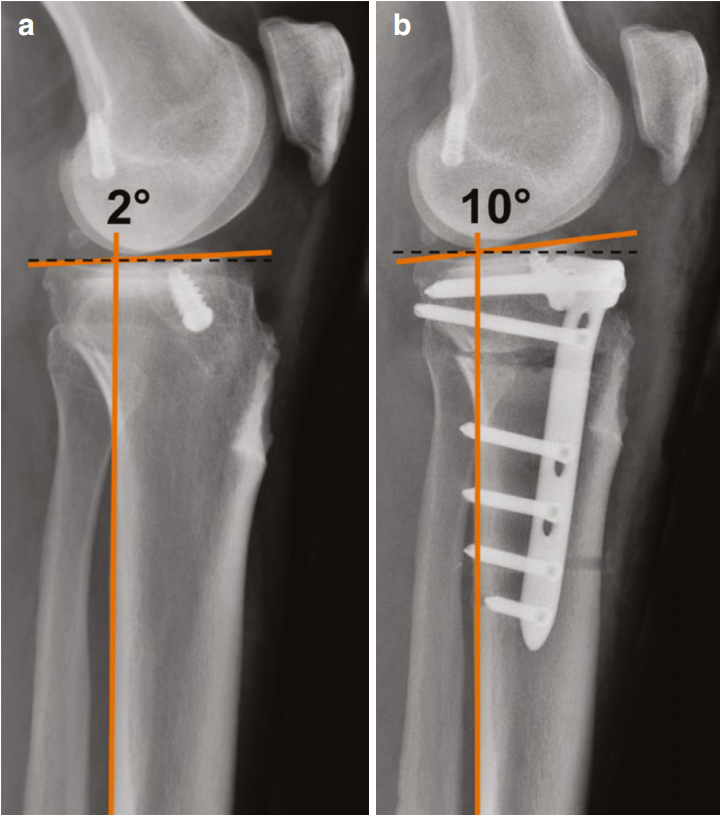

胫骨后倾角影响膝关节的前后向稳定性及活动范围,因此可在HTO术中对其进行治疗性调整。对于伴有后向或后外侧不稳定和/或过伸的膝关节内翻骨关节炎患者,我们的方案是行HTO同时增加后倾角;而对于存在前向或前内侧不稳定和/或伸直受限的患者,则在HTO同时减小后倾角。

对于存在后向/后外侧不稳定合并内侧间室骨关节炎的患者,我们将单纯的外翻屈曲位HTO(即增加后倾角)作为主要治疗方案(图10)。此类患者通常无需附加韧带重建手术。

图10 (a, b) 伴有症状性后外侧不稳定及约10°症状性过伸的患者,行屈曲位内侧开口楔形胫骨高位截骨术术前(a)与术后(b)的侧位X线片。术前2°的胫骨平台后倾角在屈曲位截骨术后增加至10°。橙色线条标记胫骨后侧皮质及胫骨平台切线,该切线与垂直于胫骨后侧皮质的虚线(黑色虚线)之间的夹角即为胫骨平台后倾角。